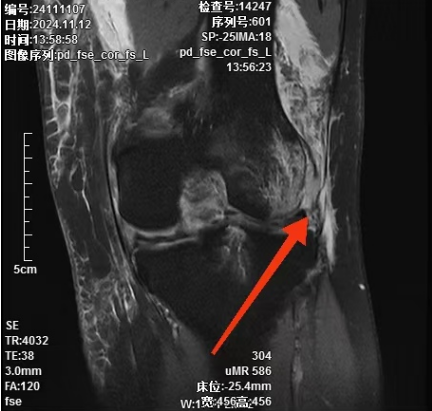

经接诊的况松主治医师细心查体并完善MRI检查后诊断为:

1. 左膝前交叉韧带断裂;

2. 左膝后交叉韧带断裂;

3. 左膝内外侧半月板Ⅲ度损伤;

4. 左膝关节内侧副韧带损伤;

5. 左股骨、胫骨骨挫伤;

6. 左股骨远端撕脱骨折。

▲术前核磁共振提示膝关节前、后交叉韧带断裂,内侧副韧带损伤